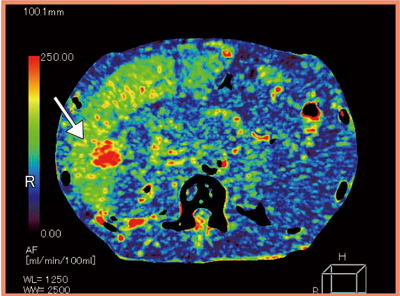

図4は,肝細胞がん症例だが,上腸間膜動脈(SMA)から行った経動脈的門脈造影下CT(CTAP)では,造影剤は脾静脈に流れて肝内には到達せず,HCCは描出されていない。同様に経肝動脈的造影CT(CTHA)でも,あまりコントラストは得られなかった。これらの画像から,HCCは乏血性であることが考えられ,TACE以外の治療法の選択が考慮されたが,CTHAのPerfusion Imageでは,周囲の肝実質よりも豊富な血流を持っていることが確認できた(図5)。TACE実施後のリピオドールCTでは,良好なリピオドールの集積を認めた。

図5 図4の症例のPerfusion Image

肝実質よりも豊富な血流があることがわかる(→)。